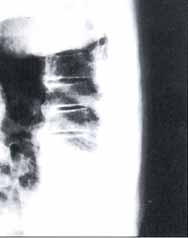

Figura 4. Radiografía Simple de Columna Tóracica baja y lumbar. Proyección AP: Osteopenia generalizada. Disminución de los espacios intervertebrales entre L3-L4 y L4-L5. Pérdida de la definición del espacio intervertebral L3-L4. Sindesmofitos marginales en toda la columna lumbar y sindesmofitos no marginales solo en el lado izquierdo.